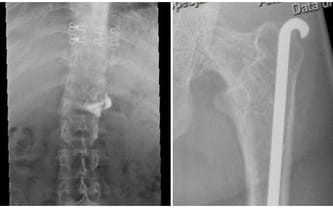

Zabieg, który polegał na wzmocnieniu (wiązką drutów gwintowanych) pękniętego biodra, skutkował dodatkowo wydłużeniem krótszej nogi! Na ten moment pozostaje mi czekać na wizytę kontrolną, na której zostanie podjęta rozmowa na temat kuracji hiperbarycznej. Czeka mnie również wizyta w Uniwersyteckim Szpitalu Klinicznym w Łodzi, na której być może zostanie podjęta zmiana leczenia pod kątem gęstości kości.

Na RTG kręgosłupa widać dużą ilość cementu wylanego poza obszar kręgosłupa. Z kolei na drugim zdjęciu widać czubek pręta Rusha. Niestety, nastąpiła szpotawość biodra lewego, co skutkuje stanem zapalnym w obrębie pręta. Wiąże się to z codziennym, ogromny bólem. Do kolejnych problemów dochodzą zmiany zwyrodnieniowe w kręgosłupie. Lekarze rozkładają ręce…